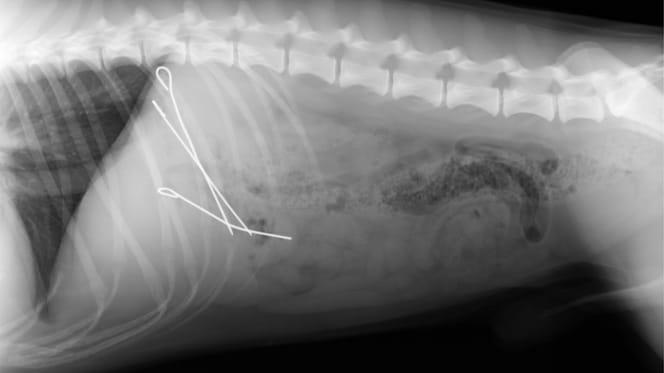

Röntgenfoto van een hond met pennen van vleesrolletjes

Daar werpt de moderne technologie eindelijk licht op de zaak. Wanneer de röntgenfoto op het scherm verschijnt, is er geen twijfel meer mogelijk. De foto toont de maag van de "dief". Zelfs voor een ongetraind oog zijn er heel duidelijk drie metalen pennen te onderscheiden.

De avond verliep dus "een beetje anders dan gepland" voor de hond en zijn baasjes, zo meldde de dierenkliniek op 25 december 2025 op Facebook. Kort daarna was namelijk een spoedoperatie nodig om de metalen pennen uit de maag van de hond te verwijderen.